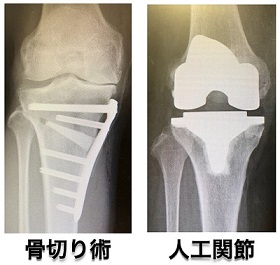

大きく分けて、骨切り術と人工関節の2種類があります。

- 若年者(50歳以下)

- ハイレベルなスポーツ(柔道、ラグビー、フルマラソンなど)、または重労働を行う場合

- 60歳以上の方

- ハイレベルなスポーツを行わない場合(ウォーキング、ハイキング、社交ダンスやヨガ、ボウリング、ゴルフはOK)

- 変形が高度、膝が伸びない場合